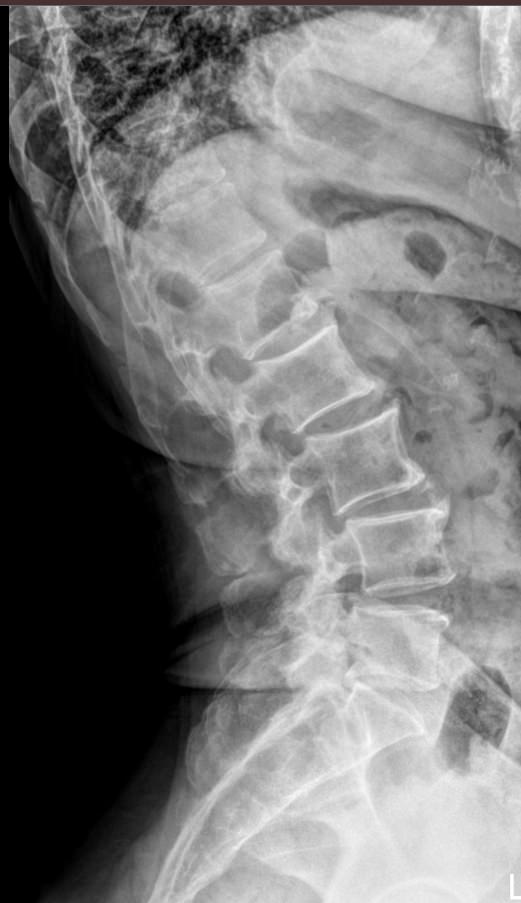

Поясничные позвонки, с 1 по 5, самые крупные во всем позвоночнике, так как удерживают большой груз ― всю верхнюю половину тела. Это последние отдельные позвонки, следующие 5 крестцовых позвонков срастаются в единую крестцовую кость. Благодаря массивности поясничный отдел может выдержать довольно сильные удары, однако травмы наблюдаются и в этом месте. Но большая часть патологий поясницы вызвана хроническими дегенеративно-дистрофическими изменениями. И чаще всего они развиваются в пояснично-крестцовом сочленении.Увидеть произошедшие с позвоночником изменения позволяет рентгенография. На снимке обычно видны все 5 поясничных, 12-й грудной и 1-й крестцовый позвонки. В некоторых случаях врачу необходим обзор крестца до уровня 3-4 позвонков. Снимки выполняются всегда в 2 проекциях.

Что покажет рентген поясничного-крестцового отдела позвоночника

• Сохранение или изменение поясничного лордоза;

• Признаки сколиоза: искривление оси позвоночника, в какую сторону, на сколько градусов, на уровне какого позвонка, с ротацией или без;

• Признаки нестабильности в поясничном отделе позвоночника

• Изменение высоты тел позвонков и межпозвонковых дисков ;

• Дистрофические изменения тел позвонков, костные разрастания, склероз;

• Наличие грыж Шморля;

• Травматические повреждения;

• Новообразования.

• Боковая ― строго боком к пластине, убрав руки за голову;